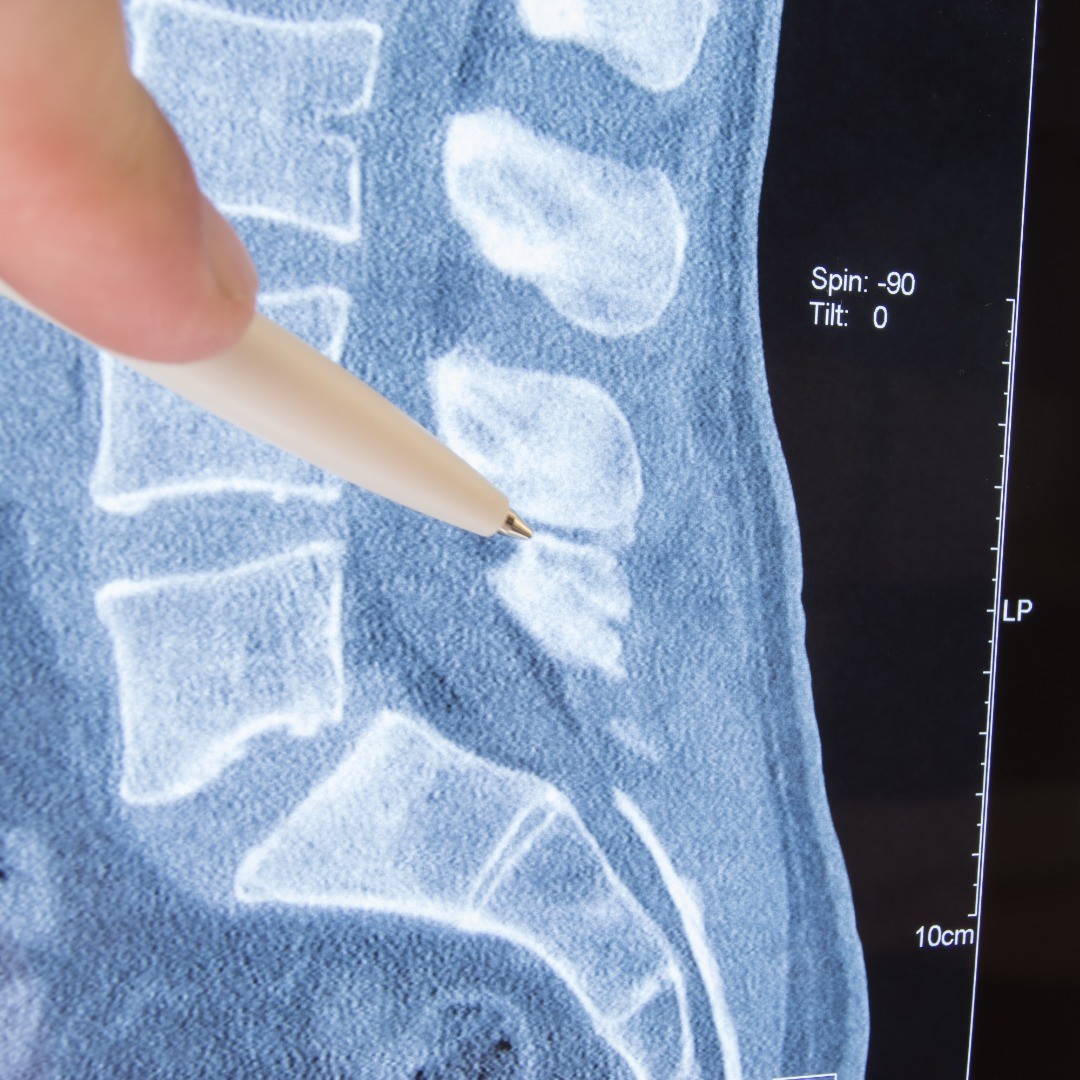

Lumbar fusion is a surgical treatment that is performed to relieve various conditions of the spine when physical therapy, medications or other treatment options are not providing necessary relief from spinal pain and discomfort. Lumbar fusion is an innovative treatment performed by our award-winning team of surgeons that may help improve your quality of life.